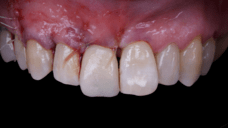

The main issue involved the upper right central incisor (tooth 1.1), which was devitalized and presented recurrent abscesses. Clinical and radiographic evaluation confirmed the presence of buccal bone wall resorption, leading to a significant defect in the alveolar ridge. This condition compromised both the hard tissue and the surrounding soft tissue, posing a challenge for achieving long-term stability and esthetic success in the anterior maxilla.

Due to the tooth’s location in the esthetic zone, the resorption and recurrent infections had a direct impact on the patient’s smile and overall confidence. She expressed dissatisfaction with the appearance of the affected tooth and emphasized the importance of restoring function and esthetics quickly. The clinical presentation highlighted the need for a treatment plan that combined immediate implant placement with simultaneous hard and soft tissue management to address the complex requirements of this case.